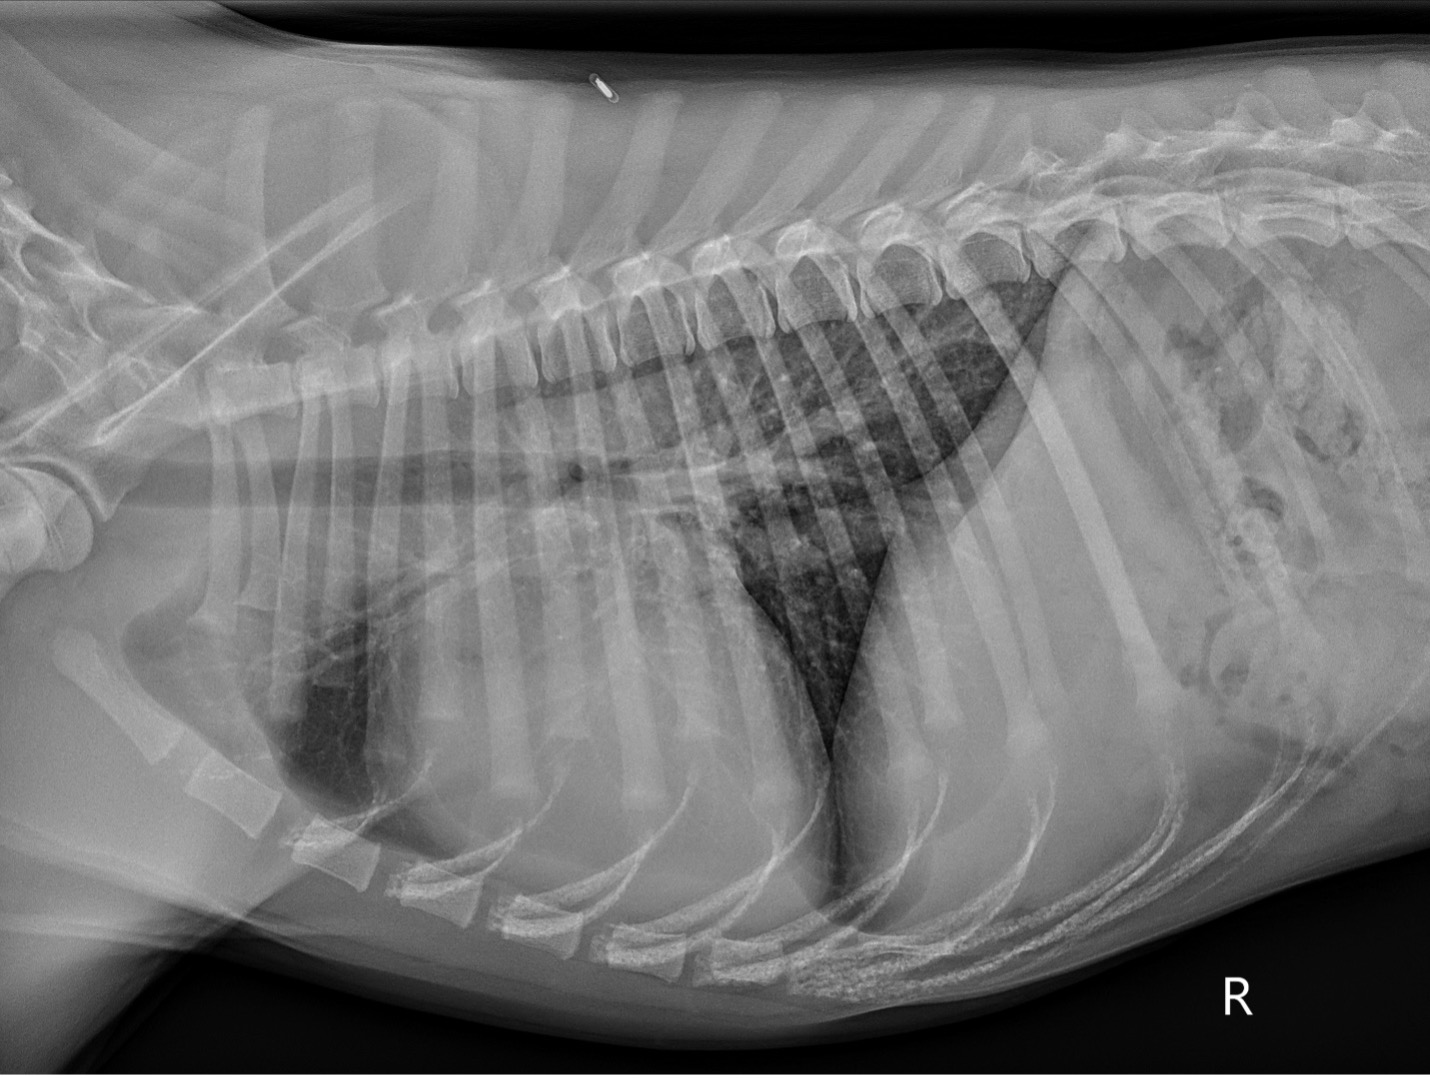

Pre-operative thoracic radiographs (Figure 1): Marked cardiomegaly with pulmonary vascular overcirculation. A mild diffuse bronchial pattern is noted. No evidence of left-sided congestive heart failure.

PICTURE: Figure 1: Pre-operative right lateral thoracic radiograph.